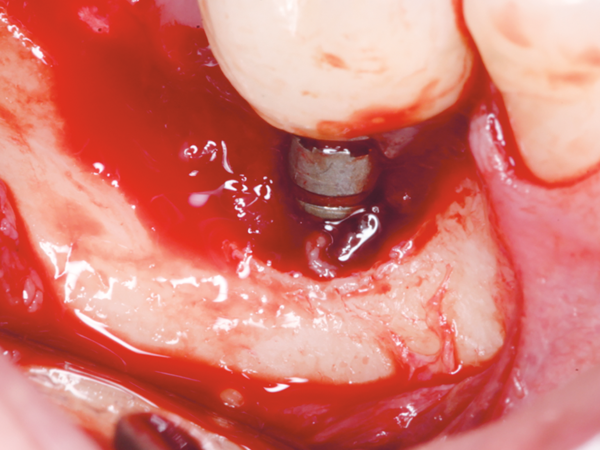

Neste contexto, em um recente estudo longitudinal de oito anos de acompanhamento1, observou-se que dos 44 pacientes e 202 implantes avaliados no período (Figura 1), o índice de sucesso foi de 96,6% e a incidência de peri-implantite (perda óssea radiográfica > 5 mm, profundidade de sondagem > 5 mm, sangramento a sondagem e/ou supuração) foi de 3%. A remodelação óssea peri-implantar foi de aproximadamente 1 mm após oito anos de avaliação (Figura 2). Entretanto, cumpre salientar que esta população apresentava um ótimo compliance, com retornos semestrais nos primeiros dois anos e anuais nos demais.

Figura 1 – Aspecto clínico da mucosa peri-implantar favorecendo o perfil de emergência de restauração implantossuportada sobre implante de conexão morse.